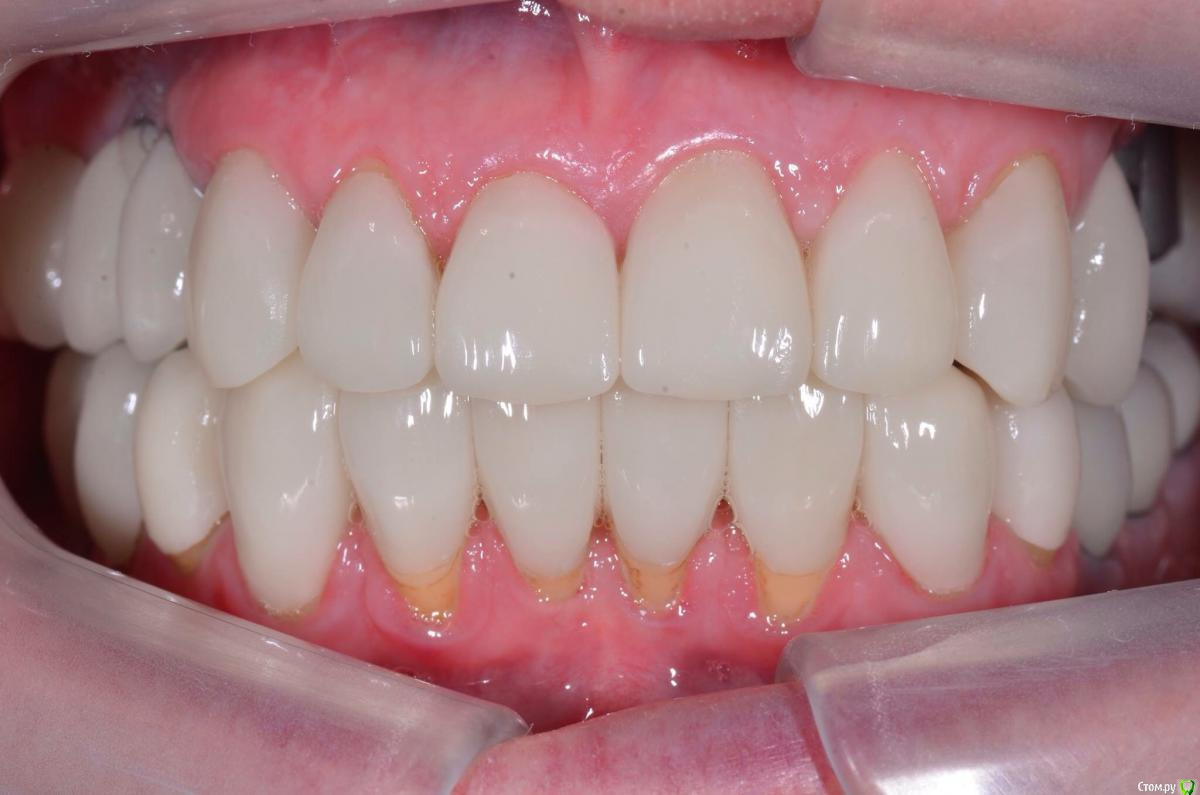

togrul Опубликовано 4 апреля, 2016 Поделиться Опубликовано 4 апреля, 2016 Добрый вечер коллеги. Восстановили зубы безметалловыми коронками Емах зубы и Циркон наслоением на имплантатах. 9 Ссылка на комментарий

togrul Опубликовано 5 апреля, 2016 Автор Поделиться Опубликовано 5 апреля, 2016 Все фотографии в день фиксации. 3 Ссылка на комментарий